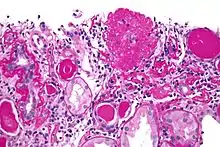

On histology, FSGS manifests as scarring (sclerosis) to segments of glomeruli; moreover, only a portion of glomeruli are affected.[7][20][21] The focal and segmental nature of disease seen on histology help to distinguish FSGS from other types of glomerular sclerosis.[21]

Diagnosis of FSGS is made by renal biopsy that includes at least fifteen serial cuts with at least eight glomeruli.[31][32] Histologic features include sclerosis (scarring) of a portion (average: 15%) of the glomerular space, with only a portion of glomeruli manifesting any sclerosis.[32]

Five mutually exclusive variants of focal segmental glomerulosclerosis may be distinguished by the pathologic findings seen on renal biopsy:[34]

Recognition of these variants may have prognostic value in individuals with primary focal segmental glomerulosclerosis. The collapsing variant is associated with higher rate of progression to end-stage renal disease, whereas the glomerular tip lesion variant has a low rate of progression to end-stage renal disease in most patients.[9] The cellular variant shows similar clinical presentation to collapsing and glomerular tip variant but has intermediate outcomes between the other two variants.[9]